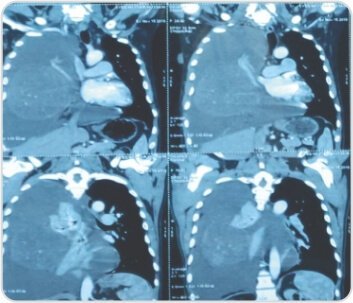

CT scan showed two large heterogenously enhancing pleural based soft tissue density lesions with neovascularity in right hemithorax measuring 14.3×13.4×11.5cm and 7.9×7.5×6.1cm. Surgery – Pleural aspiration was done and 2 litres of fluid was drained. Patient developed hemodynamic instability and was resuscitated in OT. Right posterolateral thoracotomy was performed and the tumor was removed under VATS

CT scan showing solitary fibrous right pleural tumor